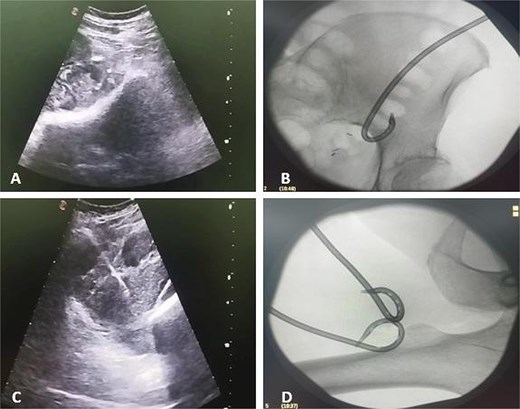

Contrast-enhanced CT demonstrated a large multiloculated IPA extending distally along the psoas sheath into the upper thigh, involving the adductor compartment (Fig. 1).

CT demonstrates multiloculated IPA with distal extension into the thigh adductor compartment. (A) Coronal CT showing a multiloculated IPA. (B) Axial CT demonstrating the psoas collection. (C) Coronal CT illustrating distal extension along the psoas sheath into the adductor compartment. (D) Axial CT of the thigh confirming distal involvement.